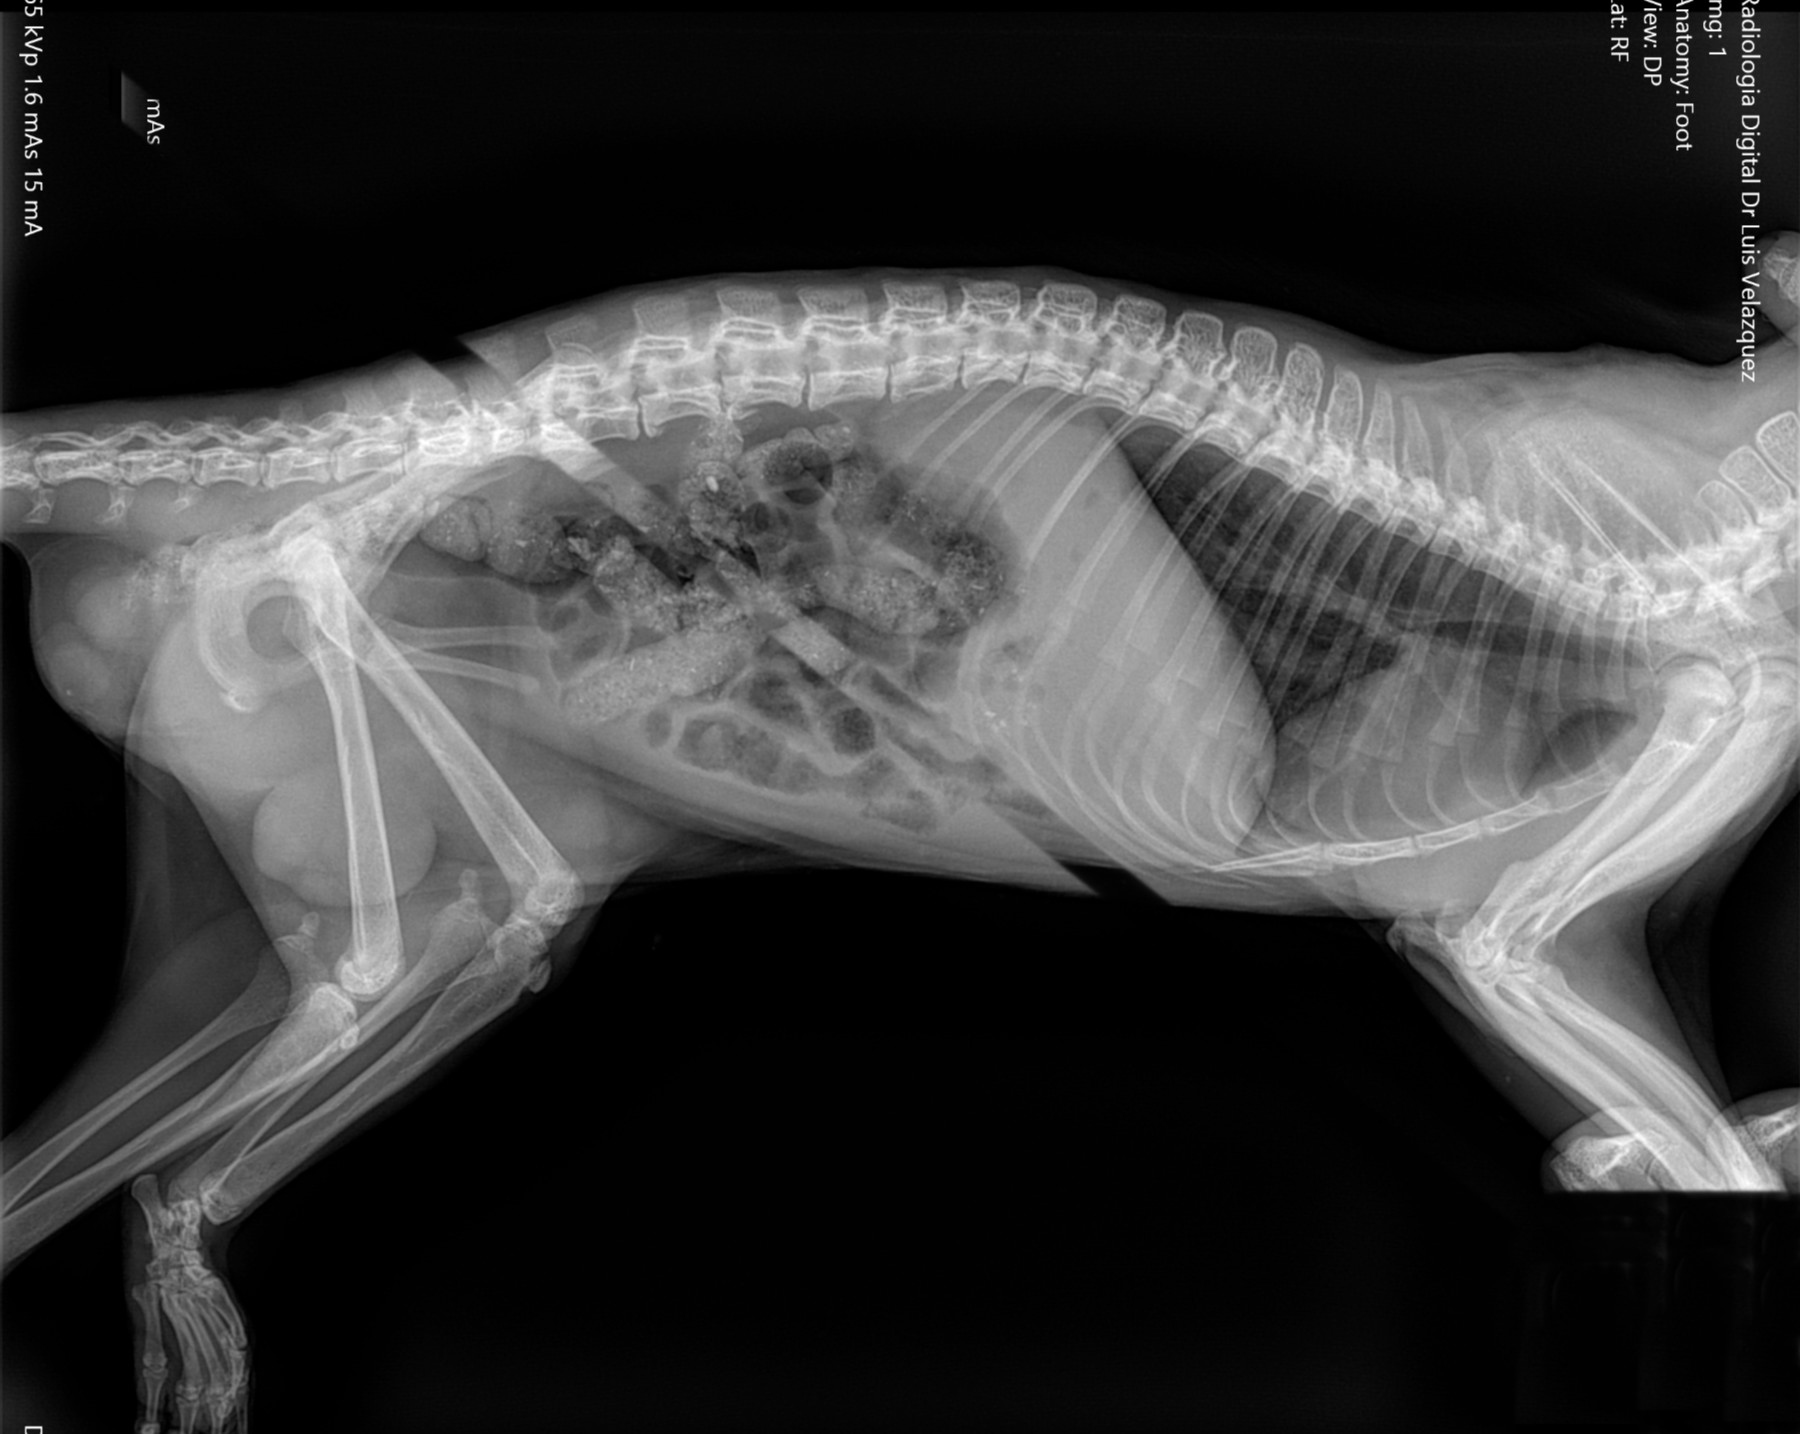

Radiología Digital como Herramienta Complementaria en el Dictamen de Bienes Muebles

Los caballos de salto, en competencia, pueden derribar obstáculos y lastimarse. Si se golpean, no siempre claudican. Considerando al calor como un signo de inflamación, se evaluaron los cambios térmicos de 6 áreas de las extremidades torácicas y pelvianas de 23 caballos de salto en nivel de competencia de 1.05 a 1.60 m de altura, por medio de termografía durante 4 días de competencia (N=2208 áreas).